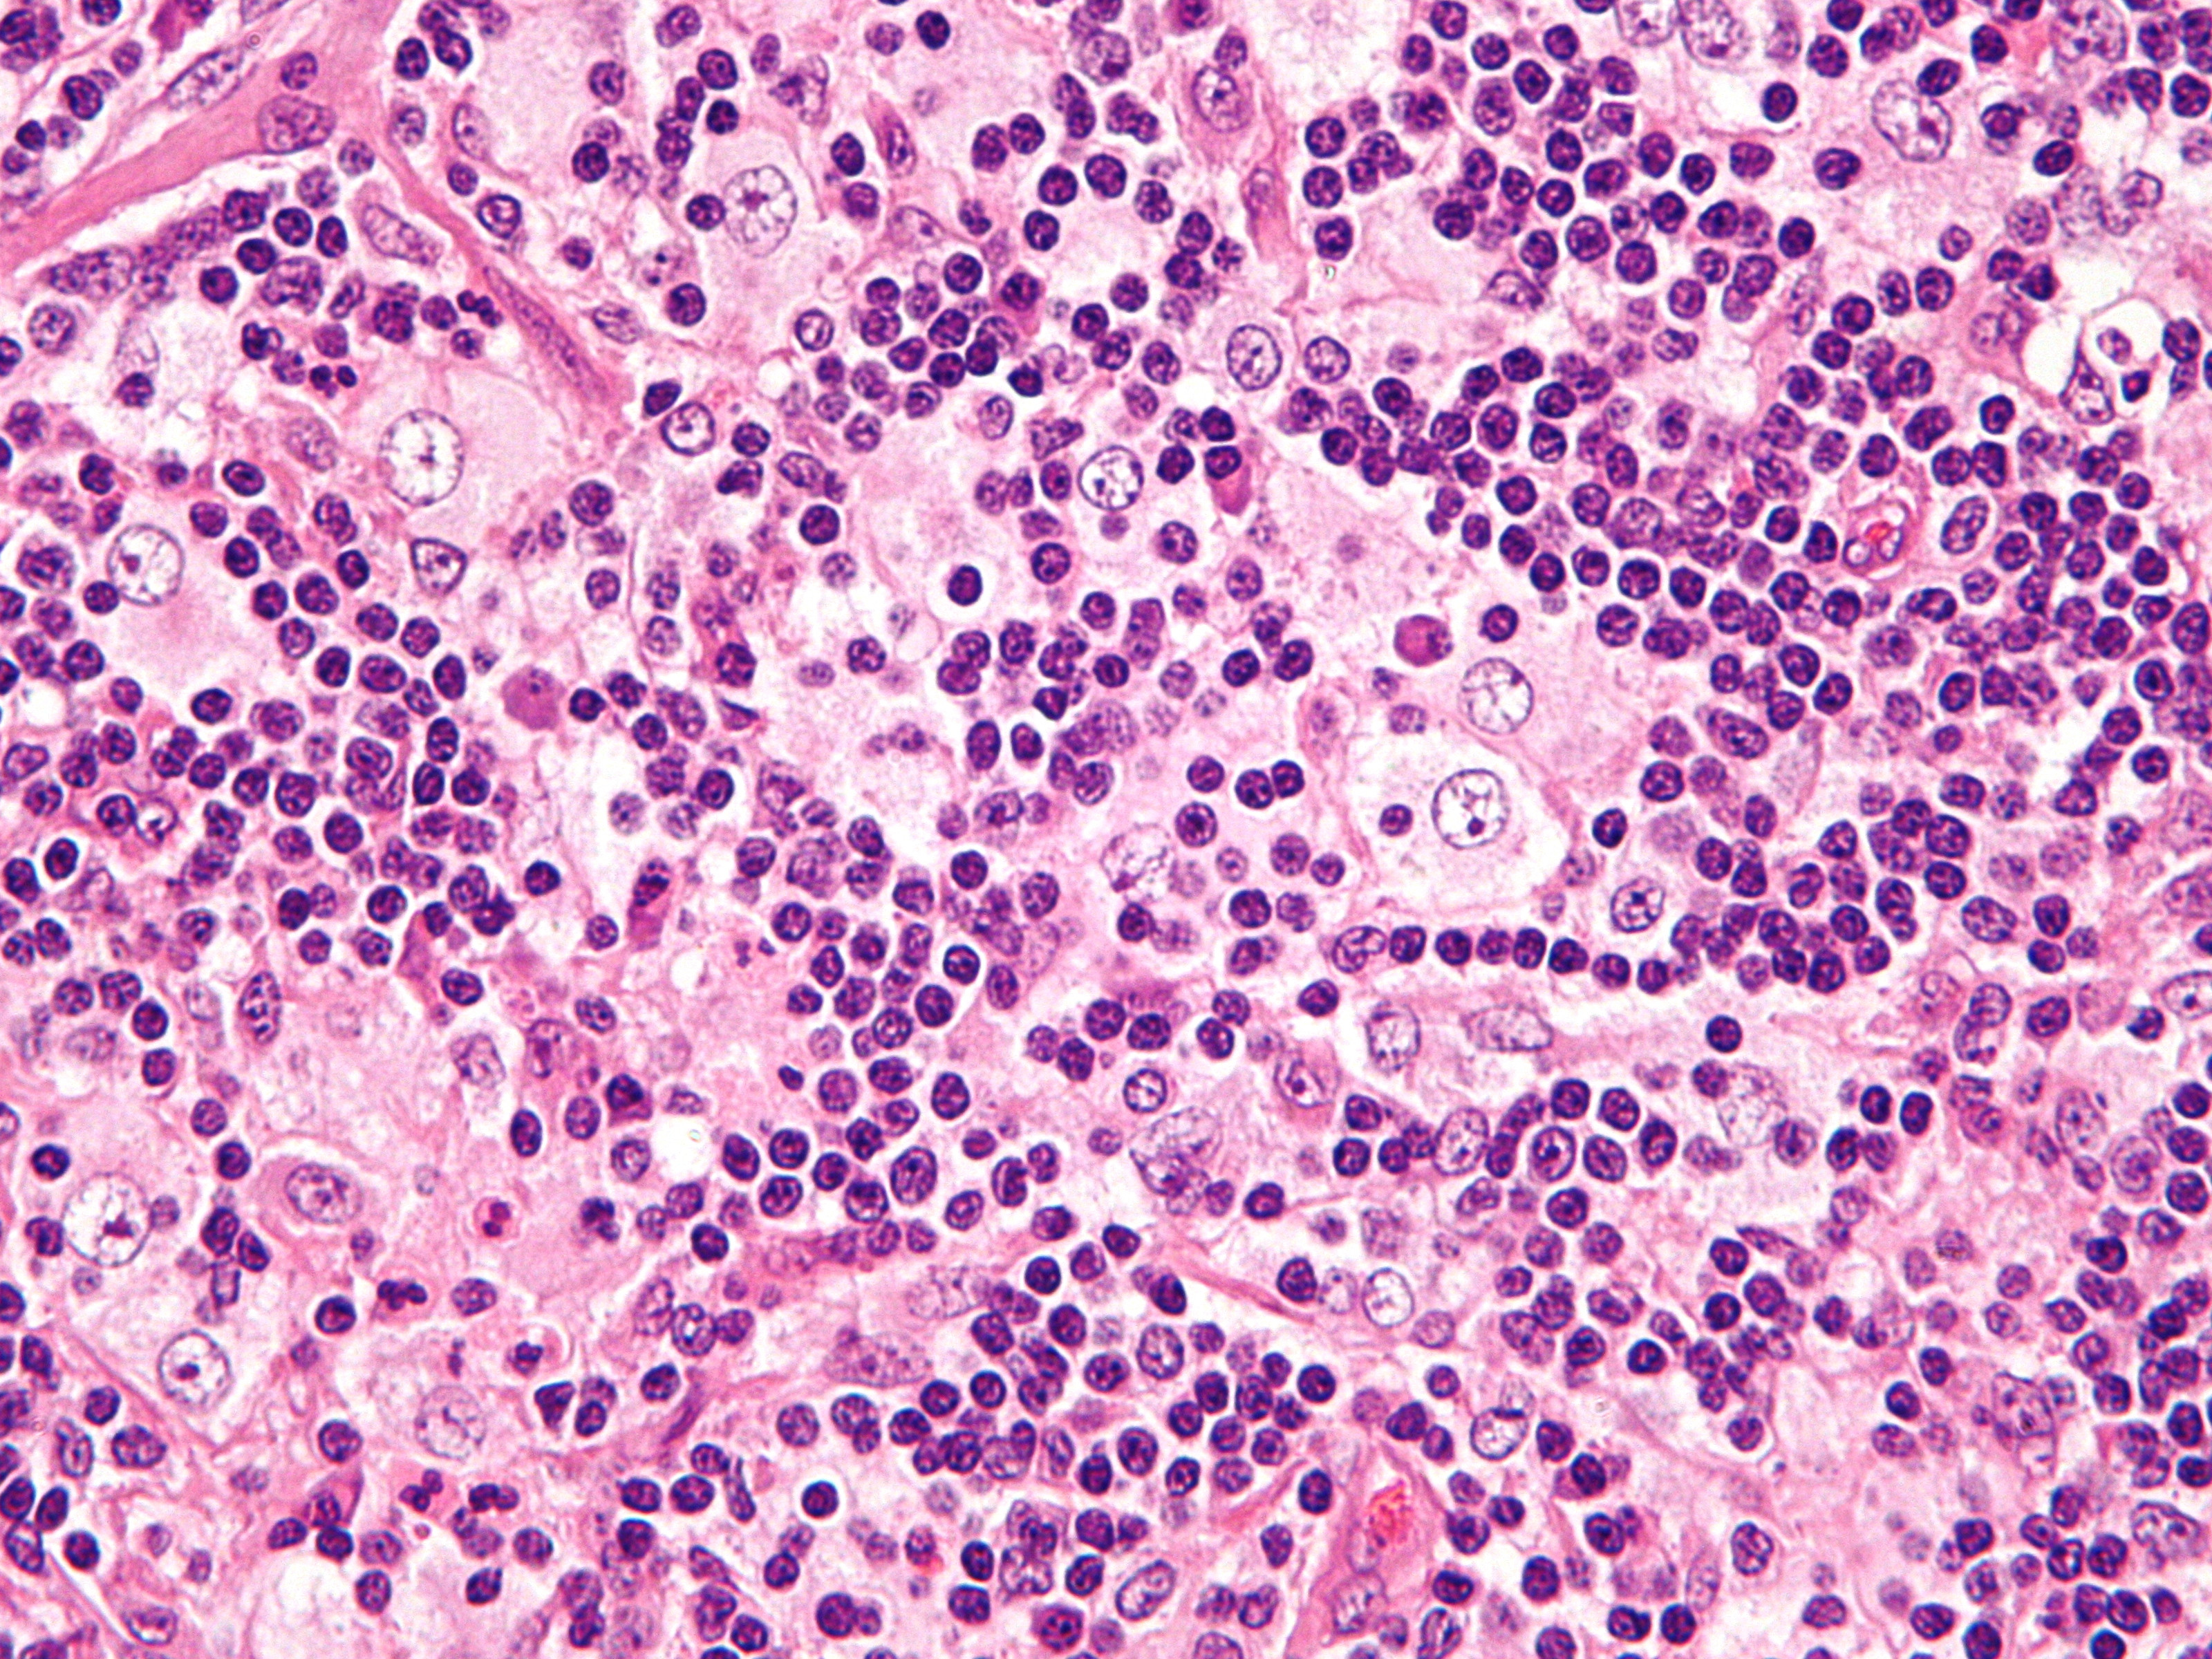

PA:

In de dermis een dicht infiltraat van histiocyten en lymfocyten, plasmacellen

en neutrofielen. histiocyten hebben grote vesiculeuze kernen, kleine nucleoli,

en een overvloedig schuimig cytoplasma. Typisch is de aanwezigheid van emperipolesis

(Rosai-Dorfman cells), het fenomeen dat binnen de grote histiocyten intacte

gefagocyteerde lymfocyten, of plasmacellen of leukocyten liggen. De histiocyten

zijn positief voor S100, CD11c, CD14, CD68, laminin 5, en lysozym. CD1a (Langerhanscellen)

is negatief. Bij elektronenmicroscopie worden geen Birbeck granula gezien.

| Rosai-Dorfman

cellen |

Rosai-Dorfman

cel |

Foto's: Michael Bonert (Nephron) en Jensflorian - Wikimedia

(Creative Commons License

3.0).